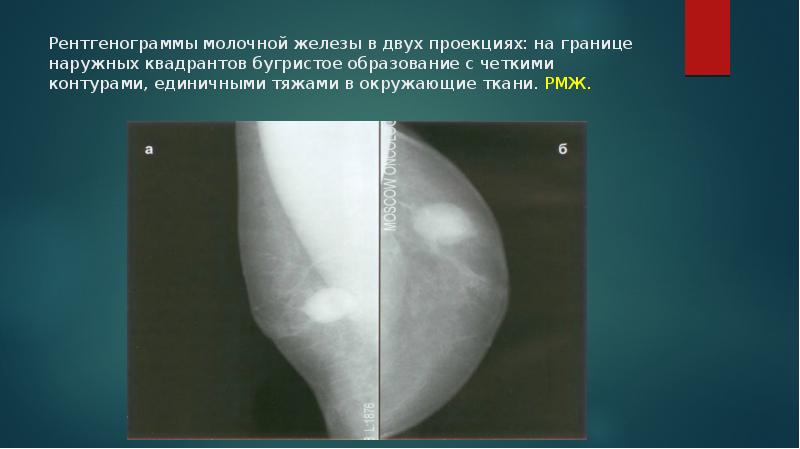

Аномалии молочной железы: медицинские примеры и визуализация

Раздел: Мудрость в деталях